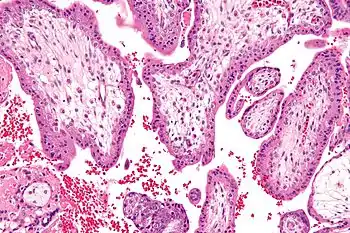

Trisomy 16 is a chromosomal abnormality in which there are 3 copies of chromosome 16 rather than two.[1] It is the most common trisomy leading to miscarriage and the second most common chromosomal cause of it, closely following X-chromosome monosomy.[2] About 6% of miscarriages have trisomy 16.[3] Those mostly occur between 8 and 15 weeks after the last menstrual period.[3]

Full trisomy 16 is incompatible with life and most of the time it results in miscarriage during the first trimester. This occurs when all of the cells in the body contain an extra copy of chromosome 16.[8]